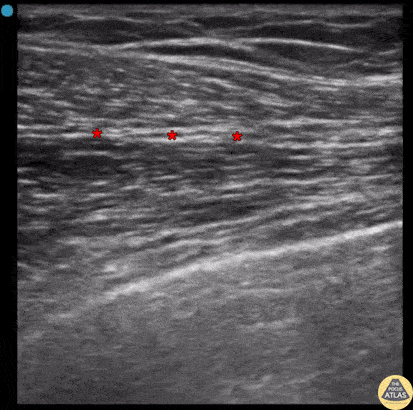

A PECS 1 block is shown here, with the needle entering from the superior and medial aspect, passing through the more superficial pectoralis major muscle and depositing anesthetic in the fascial plane between the more superficial pectoralis major and deeper pectoralis minor muscle. This nerve block provides analgesia to the anterior thoracic wall and is useful for breast or chest wall procedures such as I&D. The pleura is easily seen in this clip, which reinforces the importance of careful needle handling to avoid inadvertent pneumothorax or intrapleural infection. Dr. Nhu-Nguyen Le, Fellow Denver Health Ultrasound Fellowship